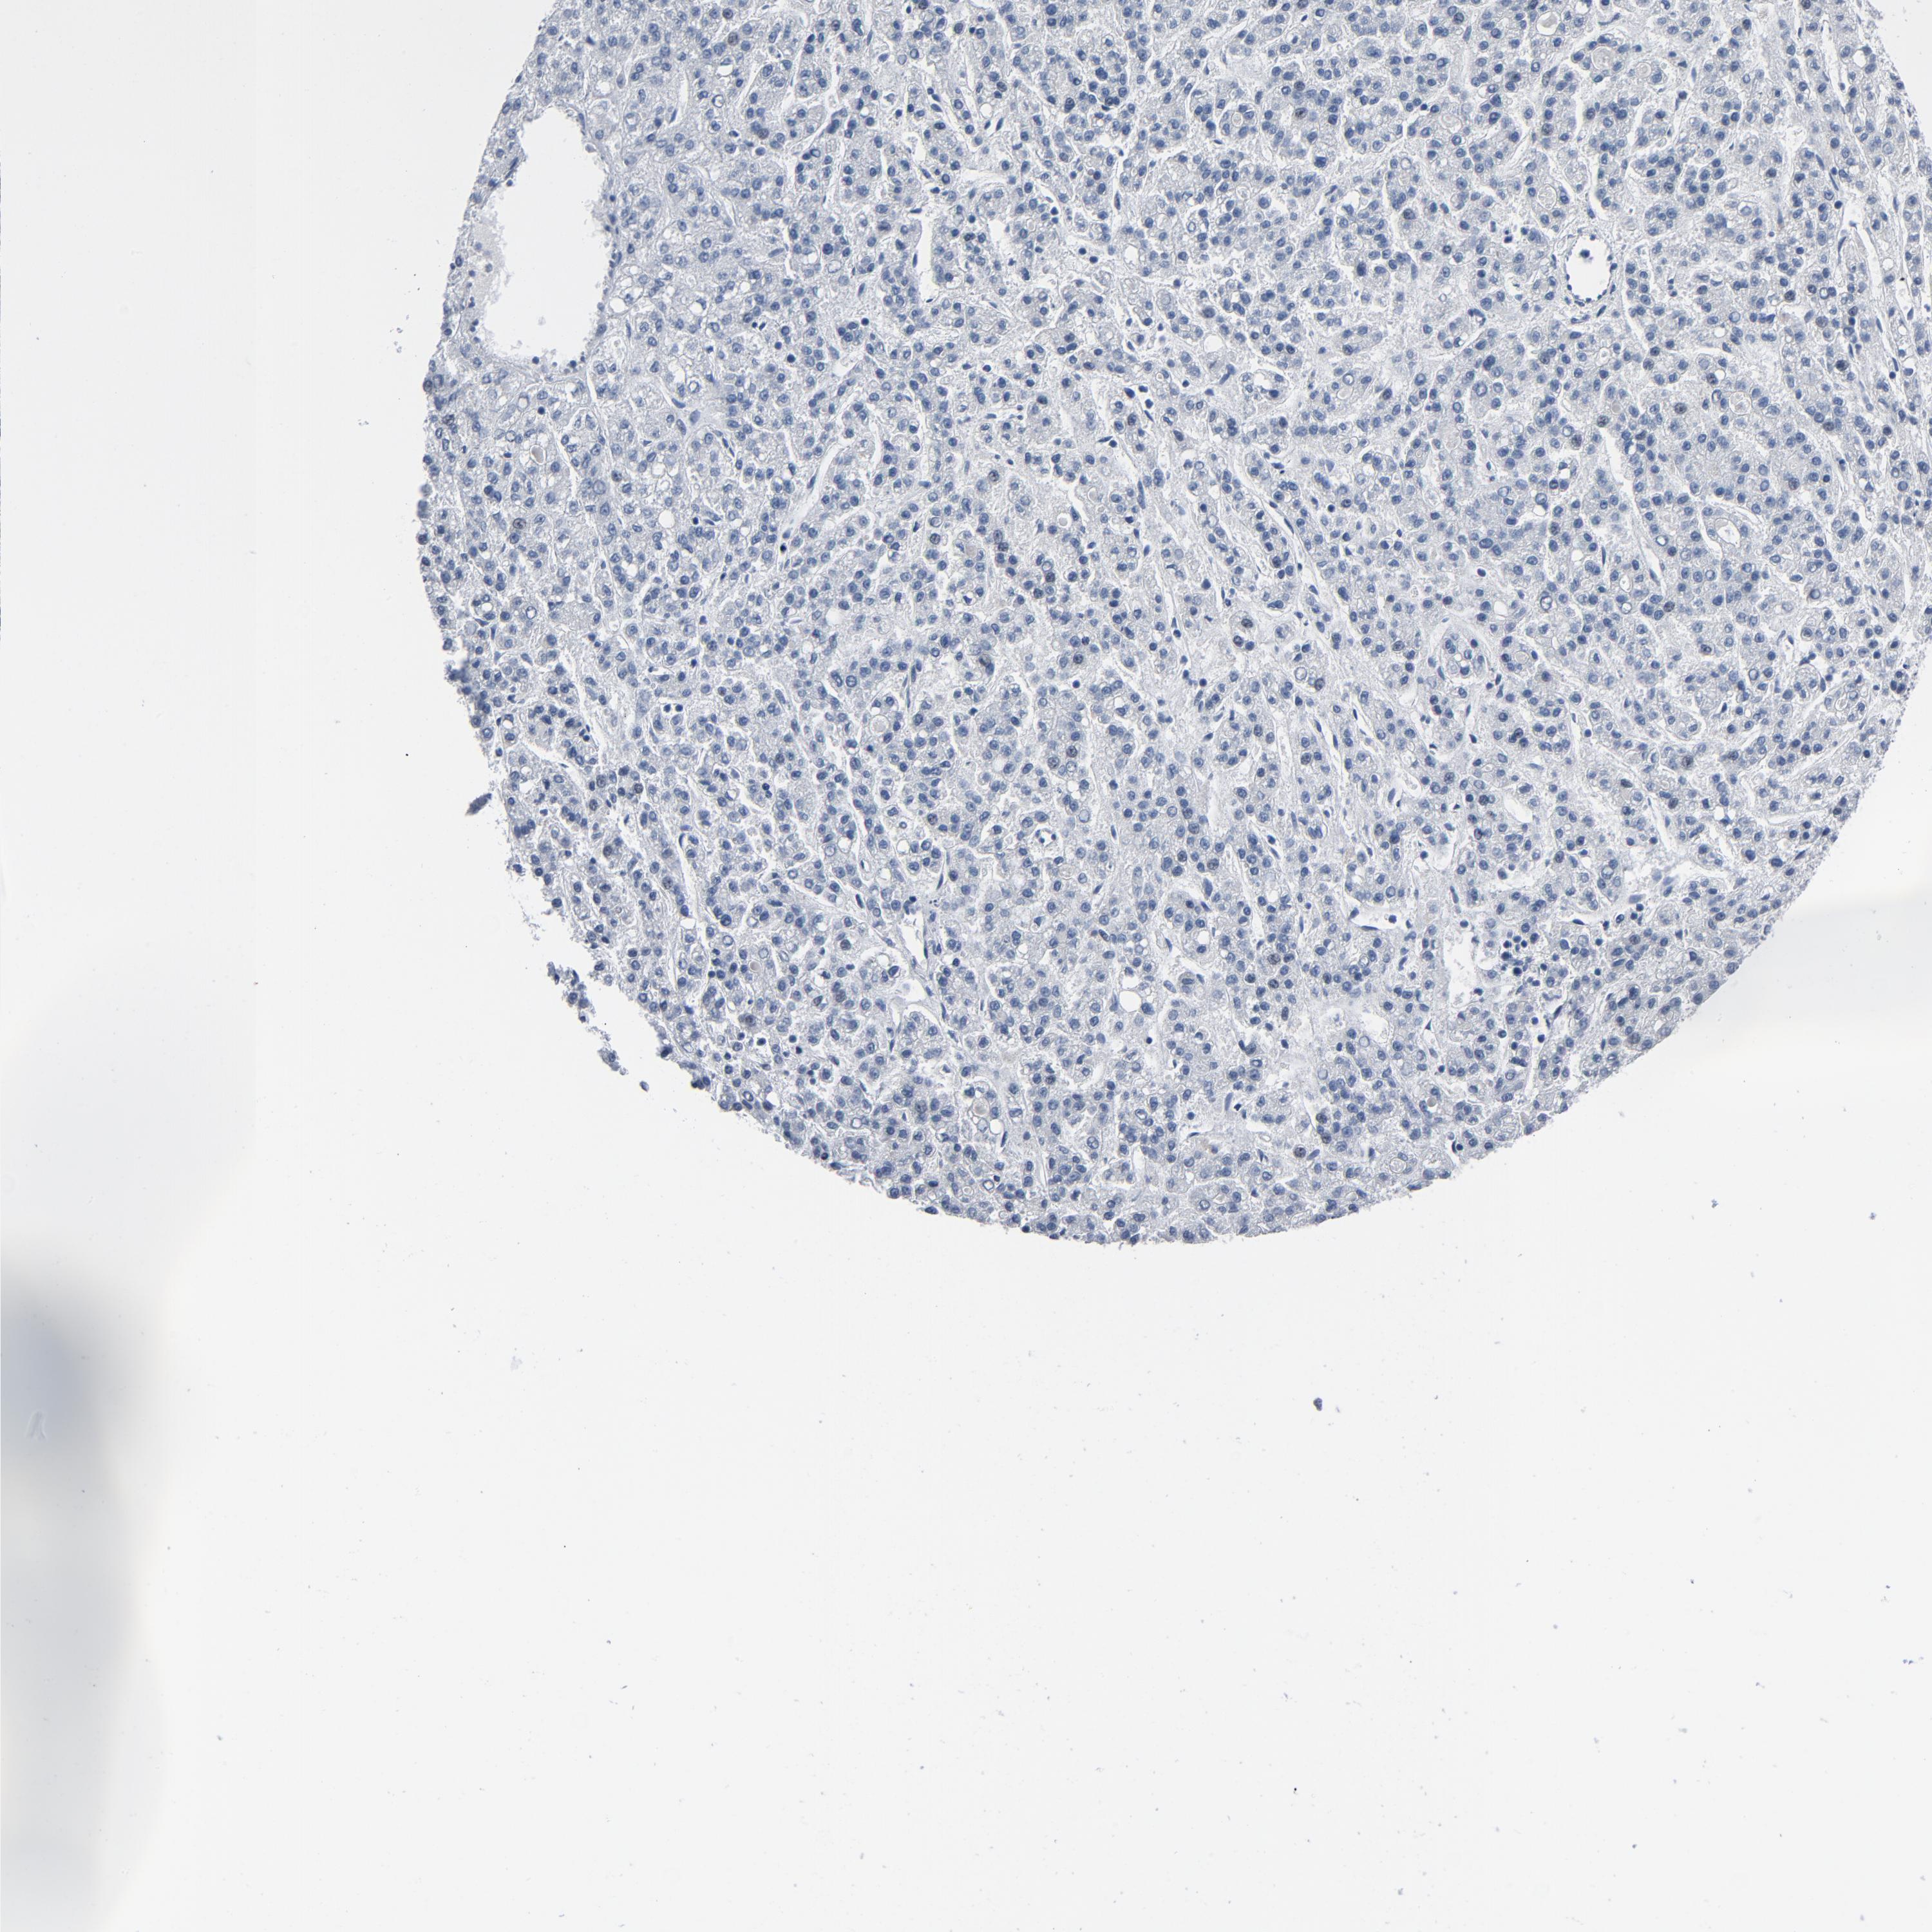

LIVER CANCER - Protein expressioni

A mouse-over function shows sample information and annotation data. Click on an image to view it in a full screen mode. Samples can be filtered based on level of antibody staining by selecting one or several of the following categories: high, medium, low and not detected. The assay and annotation is described here.

Note that samples used for immunohistochemistry by the Human Protein Atlas do not correspond to samples in the TCGA dataset.

Antibody stainingi

Antibody staining in the annotated cell types in the current human tissue is reported as not detected, low, medium, or high, based on conventional immunohistochemistry profiling in selected tissues. This score is based on the combination of the staining intensity and fraction of stained cells.

Each image is clickable and will lead to virtual microscopy that enables deeper exploration of all samples and also displays staining intensity scores, fraction scores and subcellular localization as well as patient and tissue information for each sample.

Antibody HPA003720

Cholangiocarcinoma

Carcinoma, Hepatocellular, NOS